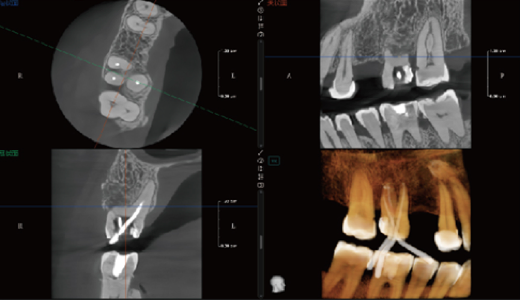

Algoritmo PD-MAR de Redução de Artefactos Metálicos

Tecnologia de correcção de artefactos líder na indústria, que elimina eficazmente artefactos persistentes em todos os cenários clínicos.

Restaura com precisão os detalhes estruturais dos tecidos.

Suporta Utilização Imediata e Comparação com Um Clique, melhorando significativamente a eficiência diagnóstica.

Elimina a necessidade de guias radiográficas, permitindo que as imagens processadas sejam utilizadas directamente na fabricação de guias cirúrgicas digitais para implantes.